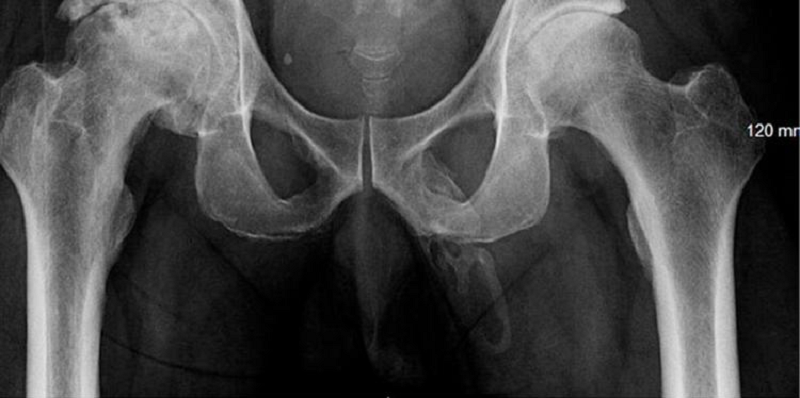

Imagens mostraram “calcificação extensa” (Foto:Reprodução/Urology Case Reports)

Houve uma “calcificação extensa em forma de placa ao longo da distribuição esperada do pênis”, escreveram os autores do artigo. Não por acaso, o paciente se queixava de dor peniana, como não outro sintoma, o diagnóstico da rara doença de Peyronie demorou.

No artigo, escrito por seis especialistas, os autores observam que a “calcificação ocorre geralmente no meio do pênis com poucos casos relatando o envolvimento de todo o eixo”